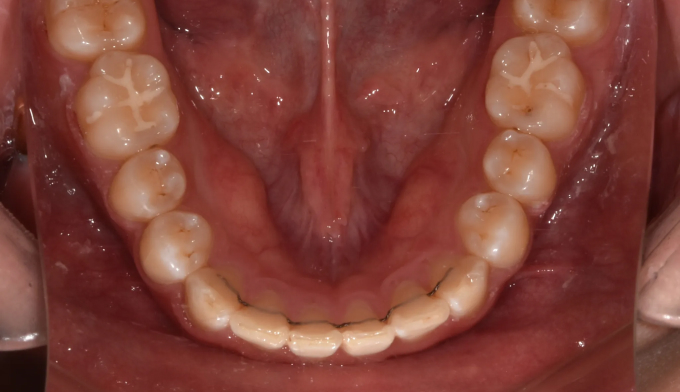

본 케이스에서는 치아 노출도를 고려하여 윗니를 위로, 아랫니를 아래로 함입하여 과개교합을 치료하였습니다.

교정기간은 총 10개월입니다.